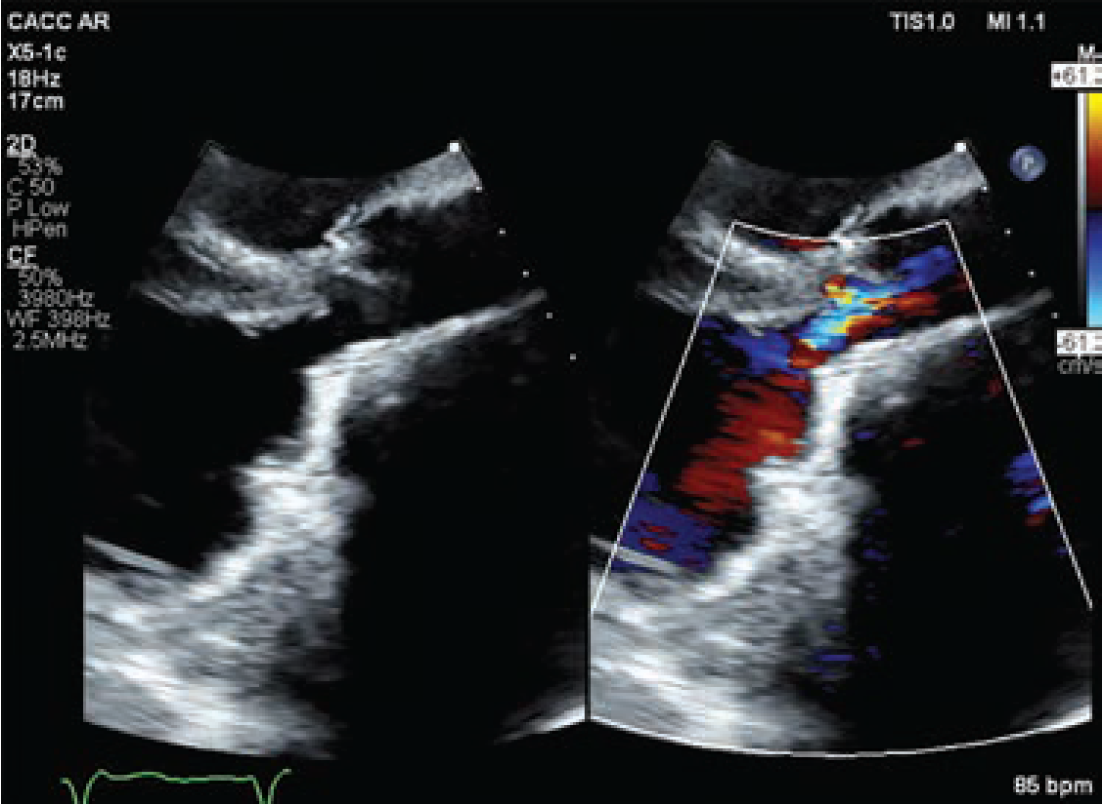

A 64-year-old female presented to the valve clinic with increasing shortness of breath, dizziness, and multiple implantable cardioverter-defibrillator (ICD) shocks over 4 months. She required 2 liters of nocturnal O2 and had a fall with significant head trauma due to syncope. She was referred to the valve clinic for consideration of a percutaneous treatment option for a subaortic membrane. She was a poor surgical candidate due to three prior sternotomies from prior valve replacements. Additionally, she presented with chronic atrial fibrillation, a history of stroke, a thromboembolic disorder, and a left ventricular outflow tract (LVOT) gradient of 80 mmHg. A transesophageal echocardiogram (TEE) revealed that she had an ejection fraction (EF) of 20% (Figure 1). Her case was complex and high risk.

Baseline computed tomography imaging revealed the patient had an enormous left atrium (volume of 798 cm3), a narrow LVOT, and an 8.5 mm subaortic membranous band. The team determined that multimodality imaging (TEE, transthoracic echocardiogram [TTE], and intracardiac echocardiography [ICE]) would be required for an endovascular fix due to shadowing artifacts from the mechanical mitral valve and the tricuspid ring, as well as distortion from the large left atrium.